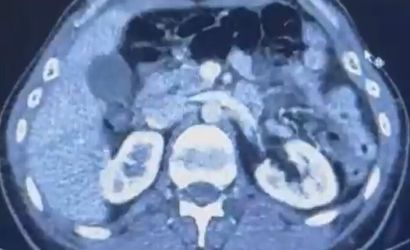

Kayseri Şehir Hastanesi'nde yapılan iç beden muayenelerinde, şüphelilerin mide kısmında 50 adet kapsül halinde toplam 554 gram uyuşturucu madde bulunduğu tespit edildi.

ŞÜPHELİLERİN MİDESİNDE KAPSÜL ŞEKLİNDE YARIM KİLO UYUŞTURUCU MADDE ELE GEÇİRİLDİ.